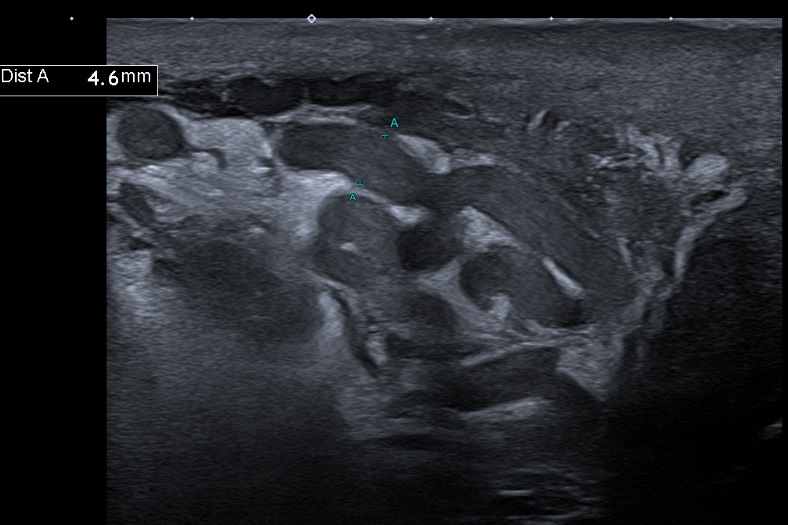

Varicoceles are very common and sometimes not properly reported. Nonetheless, US examination allows for going much further than detection. The ESUR group provides useful hints for better reports.

Article: Ultrasound evaluation of varicoceles: guidelines and recommendations of the European Society of Urogenital Radiology Scrotal and Penile Imaging Working Group (ESUR-SPIWG) for detection, classification, and grading